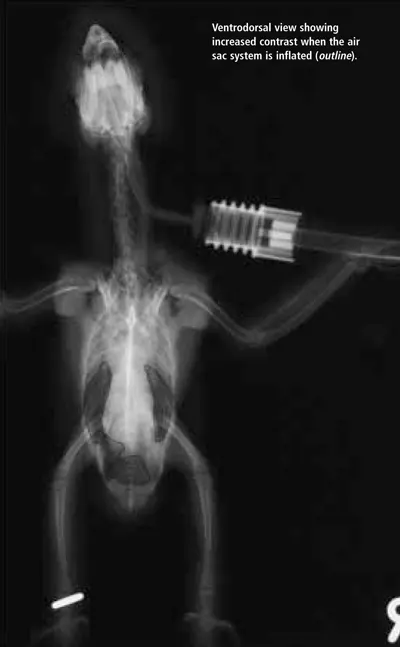

The avian respiratory system is extensive and complex. Becoming familiar with the normal presentation of respiratory anatomy through use of different imaging techniques will enhance a clinician's ability to make a diagnosis. This is the first of two articles using radiographic images and computed tomography (CT) to compare normal respiratory structures of the avian respiratory system. Note that the size of the patient dictates the size of the CT image. In this case, the patient is very small; thus, the images have become somewhat blurry with enlarging. Nevertheless, contrast is an important factor in CT imaging and the structures are quite clear. This article focuses on the body; the next part will address the head. For larger images, please click on the PDF icon at the top of the page to download the print version of the article in its entirety.

A ventrodorsal radiograph of a bird shows an inflated air sac system, highlighting increased contrast in the thoracic region. The image provides a clear view of the skeletal structure and respiratory anatomy, essential for veterinary assessment.